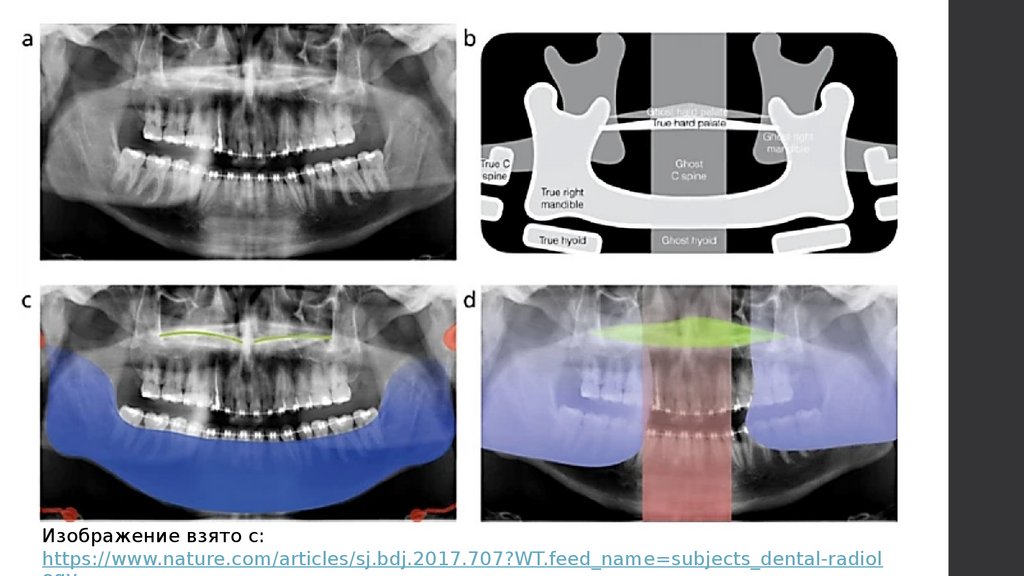

Реальные, двойные, призрачные изображения

на панорамных рентгеновских снимках

13.

Реальные, двойные, призрачные

изображения на панорамных

рентгеновских снимках

11.

Реальное + призрачное

изображение

Призрачное изображение

Реальное

Два реальных

изображения по

бокам + одно

призрачное в центре